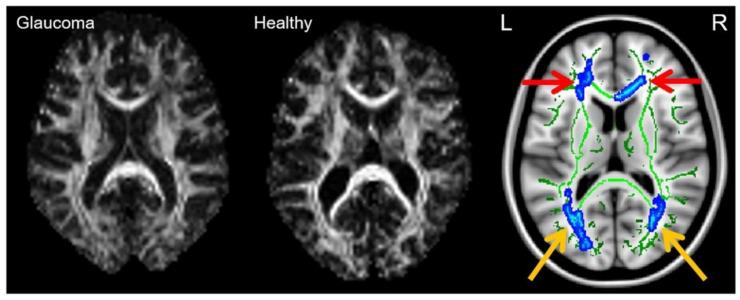

Glaucoma is a group of ophthalmologic conditions characterized by progressive retinal ganglion cell death, optic nerve degeneration, and irreversible vision loss. While intraocular pressure is the only clinically modifiable risk factor, glaucoma may continue to progress at controlled intraocular pressure, indicating other major factors in contributing to the disease mechanisms. Recent studies demonstrated the feasibility of advanced diffusion magnetic resonance imaging (dMRI) in visualizing the microstructural integrity of the visual system, opening new possibilities for non-invasive characterization of glaucomatous brain changes for guiding earlier and targeted intervention besides intraocular pressure lowering. In this review, we discuss dMRI methods currently used in visual system investigations, focusing on the eye, optic nerve, optic tract, subcortical visual brain nuclei, optic radiations, and visual cortex. We evaluate how conventional diffusion tensor imaging, higher-order diffusion kurtosis imaging, and other extended dMRI techniques can assess the neuronal and glial integrity of the visual system in both humans and experimental animal models of glaucoma, among other optic neuropathies or neurodegenerative diseases. We also compare the pros and cons of these methods against other imaging modalities. A growing body of dMRI research indicates that this modality holds promise in characterizing early glaucomatous changes in the visual system, determining the disease severity, and identifying potential neurotherapeutic targets, offering more options to slow glaucoma progression and to reduce the prevalence of this world's leading cause of irreversible but preventable blindness.

青光眼是一组眼科疾病,其特征为视网膜神经节细胞进行性死亡、视神经变性以及不可逆的视力丧失。虽然眼压是唯一可在临床上进行调节的风险因素,但青光眼在眼压得到控制的情况下仍可能继续发展,这表明还有其他主要因素参与了疾病机制。最近的研究表明,先进的扩散磁共振成像(dMRI)能够可视化视觉系统的微观结构完整性,为青光眼性脑改变的非侵入性特征描述开辟了新的可能性,从而除了降低眼压之外还能指导更早且有针对性的干预。在这篇综述中,我们讨论目前在视觉系统研究中使用的dMRI方法,重点关注眼睛、视神经、视束、皮层下视觉脑核、视辐射和视觉皮层。我们评估传统的扩散张量成像、高阶扩散峰度成像以及其他扩展的dMRI技术如何能够在青光眼以及其他视神经病变或神经退行性疾病的人类和实验动物模型中评估视觉系统的神经元和神经胶质完整性。我们还将这些方法与其他成像方式的优缺点进行比较。越来越多的dMRI研究表明,这种成像方式在表征视觉系统早期青光眼性改变、确定疾病严重程度以及识别潜在的神经治疗靶点方面具有前景,为减缓青光眼进展以及降低这种全球不可逆但可预防失明的主要原因的患病率提供了更多选择。